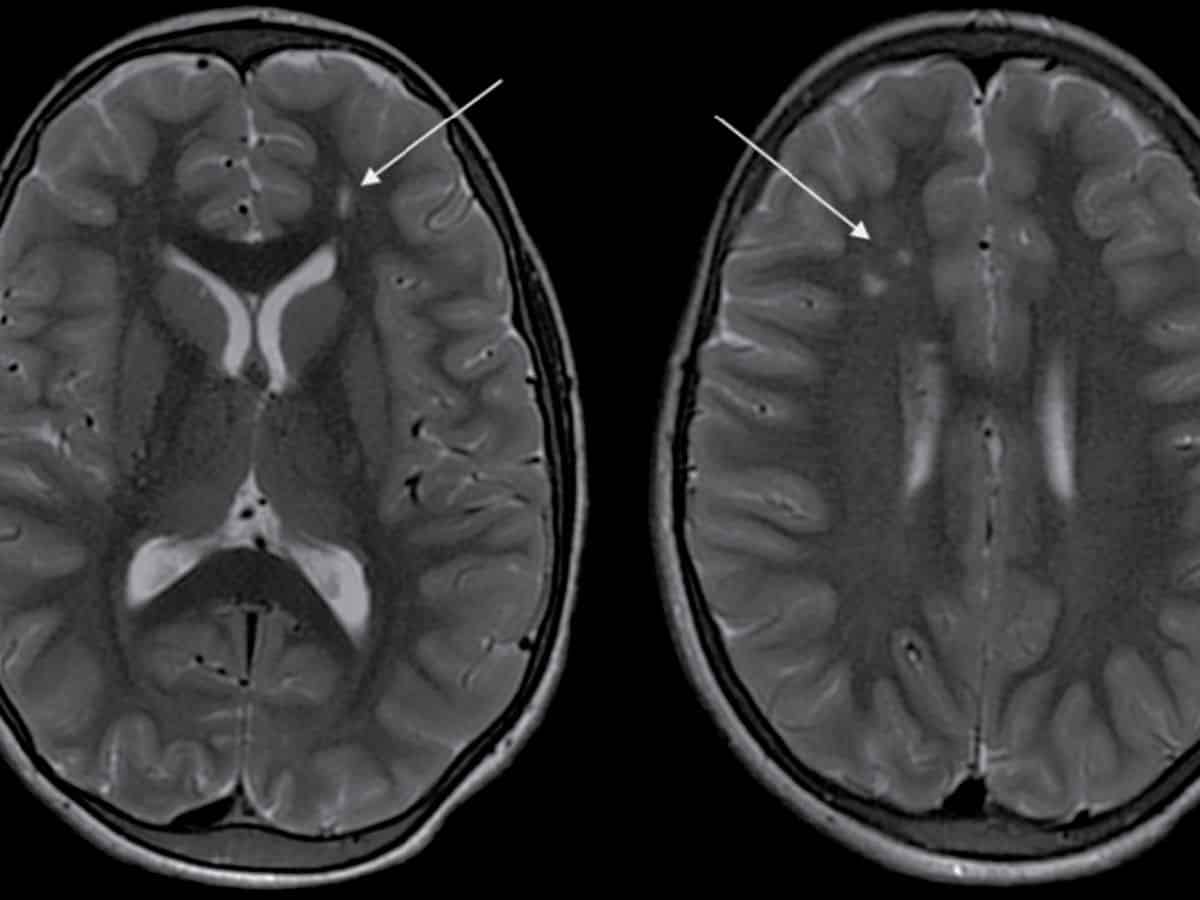

Arjun (name changed) experienced an episode of seizure a year back which was progressively followed by a decline in his ability to see and weakness on the left side of his body over the course of the year. A CT Angiogram at Aster Whitefield Hospital showed a “puff of smoke” appearance - a hallmark sign of Moyamoya disease, hence confirming the diagnosis.

This rare and unique disease mostly affects children around the age of 10 years and adults around the age of 40 years while progressing without warning, necessitating prompt and precise medical intervention. Moyamoya disease causes narrowing of key brain arteries, prompting the brain to form smaller compensatory blood vessels to meet its oxygen needs. These new vessels, however, are often insufficient, appearing as a “puff of smoke” in imaging scans. When the brain’s demand for blood outpaces the supply, patients experience strokes or other neurological events, as in Arjun’s case. Left untreated, Moyamoya can lead to recurring strokes, disability, and even death, making early diagnosis critical to altering the disease's course.